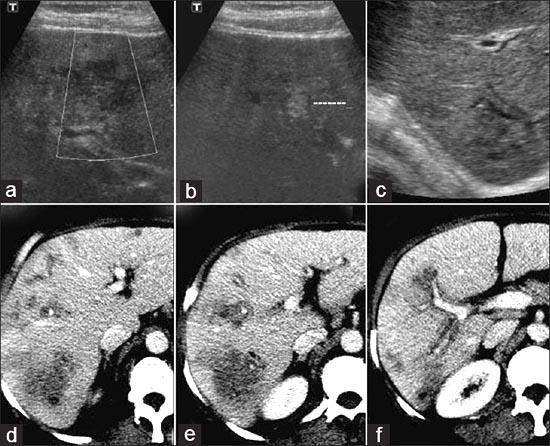

Trong các nghiên cứu mở rộng đa trung tâm về bệnh SLGL cho thấy chẩn đoán hình ảnh học đề cập đến nhu mô gan (pha cấp của ấu trùng sán khi xâm nhập vào nhu mô gan), CT-scaner giúp chỉ ra các vùng thương tổn chùm dưới bao gan và tính chất giảm âm. Trong khi đó chụp cộng hưởng từ (MRI) cũng cho các hình ảnh tương tự như trong CT-scanner nhưng hình ảnh rõ nét và đặc trưng hơn rất nhiều, giúp xác định và mô tả tổn thương đầy đủ hơn. Trong pha đường mật, CT scanner cho thấy hình ảnh dãn ống dẫn mật ở vị trí trung tâm sán nằm và có sự giảm âm ở vùng ngoại vi (vết) và siêu âm có giá trị xác định con sán di động khi chúng còn di chuyển trong hệ đường mật.

Một vài nghiên cứu trên thế giới cho thấytrên siêu âm và CT scanner có tổn thương đa ổ, mật độ giảm với sự tập trung các bóng mờ hình cục ở thuỳ gan (P) và dãn rộng các nhánh đường mật trong gan, nhất là thuỳ (P). Một số nhánh đường mật dãn có hang, kích thước trung bình. Đường mật bị bao quanh bởi một phần giảm mật độ làm thành từng ổ. Những điều tìm thấy này là biểu hiện của tắc nghẽn đường mật do biến chứng viêm đường mật, khi đó sẽ tạo thành các ổ hoại tử trong gan do quá trình tắc nghẽn này.

Tổn thương hệ gan mật qua hình ảnh siêu âm cho hình ảnh bất thường liên quan đến nhu mô gan (giai đoạn cấp) thường gặp nhất và tổn thương đường mật (giai đoạn mạn tính) với biểu hiện hình ảnh đa dạng, trong đó tổn thương nhu mô dạng tăng âm giống lưỡi liềm không kèm bóng lưng rất đáng chú ý. Phân tích chi tiết bệnh SLGL trên phụ nữ mang thai trong từng giai đoạn (trước 4 tháng và sau 4 tháng):

Trong giai đoạn cấp (thời gian mắc bệnh < 4 tháng)

Siêu âm cho thấy 3 loại tổn thương ở giai đoạn cấp, loại thứ nhất là hình ảnh nhu mô gan không đồng nhất (87,23%), đôi khi chỉ một ổ tổn thương chiếm chủ yếu, hoặc kèm tổn thương cạnh bao Glisson (9,57%), tụ dịch hoặc máu dưới bao gan (6,38%); tổn thương túi mật dưới dạng dày xơ và khuyết loét nông thành túi mật (5,32%) và các đường mật (2,13%). Đặc biệt, có 2 PNMT chưa phát hiện tổn thương (2,13%). Các tổn thương nhu mô thường có bờ không rõ ranh giới giữa nhu mô lành và bệnh kèm tính chất tăng, giảm, hợp âm khác nhau: trong đó giảm âm chiếm chủ yếu (91,49%), hỗn hợp âm (87,23%) và dạng tăng âm ít gặp hơn (3,19%), xen lẫn tổn thương giảm âm, hợp âm còn có các vùng trống âm (chứa dịch, máu) khá nhiều, nhất là các bệnh nhân đến muộn (46,81%). Kết quả này phù hợp với một số nghiên cứu tại Iran, Thỗ Nhĩ Kỳ, Tây Ban Nha, Ai Cập (Eisenscher và cs., 1998; Cauquil P và cs., 1996; Huỳnh Hồng Quang và cs., 2006); tổn thương đa dạng thường là microabces đã hoại tử hoặc vừa hoại tử vừa tiến triển, có xu hướng lan rộng, tụ thành một khối dịch lớn. Đặc biệt, tổn thương nhu mô gan thường có nhiều “mắt nhỏ”, dạng nốt, nếu là hình ảnh giảm âm hoặc xen kẻ trống âm ở chính giữa thì rất khó phân biệt với các dạng áp xe hay khối tân sinh (neoplasm) nhất là khi đã xuất hiện đặc điểm hoạt tử trung tâm (Huỳnh Hồng Quang và cs., 2005; WHO, 2007). Khi tổn thương nhu mô gan, các thùy và hạ phân thùy (HPT) đều có “cơ hội” bị tổn thương, nhưng vị trí gặp ở gan phải là 80,32% nhiều hơn gan trái chỉ có 7,47%. Trong một nghiên cứu của Richter và cộng sự (2006) cũng cho biết tỷ lệ tổn thương gan (P) và (T) lần lượt 92,02% và 6,3%.

Loại tổn thương thứ hai gặp trong giai đoạn cấp là các “khoang” hoặc có nhánh trông giống đường hầm. Đây là những hình ảnh có vòng ngoại vi ngoằn ngoèo, khúc khủy do quá trình sán Fasciola sp. di chuyển trong nhu mô (Didier D và cs., 1985; Cooperberg và cs., 1987; Huỳnh Hồng Quang và cs., 2007). Loại tổn thương thứ ba là một tổn thương nhu mô nhưng sát bao gan, khi hoại tử đã vở ra bên ngoài được bao gan bọc lại, loại ổ này có nguy cơ đe dọa vở nếu không can thiệp kịp thời (6,38%) hay gọi là giả u mạch (“pseudohematoma”). Đôi khi, siêu âm còn phát hiện một số hình ảnh ít điển hình hơn như giả u hạt, hoại tử có tăng âm ngoại vi, áp xe không điển hình hoặc dạng hốc u mạch thể hang (carvenous hemangioma).

Trong giai đoạn mạn tính

Hình ảnh siêu âm điển hình thường là đa ổ nhỏ, li ti có thể vừa gặp trong nhu mô gan vừa gặp trong hệ đường mật (3,13%), cả ống mật chủ; nhưng phần lớn là các vệt thả nổi (floating) hoặc vết dính (trace) tăng âm di động bên trong túi mật hoặc ống mật chủ mà không kèm bóng cản (2,13%), có thể đó là sán chuyển động hoặc xác sán chết lưu lại.

Một dấu hiệu nữa không đặc trưng cho giai đoạn mạn tính là hình ảnh dãn, phù nề và dày thành túi mật, đường mật (2,13% và 1,06%) không đồng đều, dấu hiệu này cũng thường gặp trong bệnh cảnh viêm xơ đường mật do sán (Mansoeu G. và cs., 2002; Huỳnh Hồng Quang và cs., 2005). Nói chung, ở giai đoạn mạn tính thì tổn thương hệ đường mật nhiều và phổ biến hơn nhu mô gan.